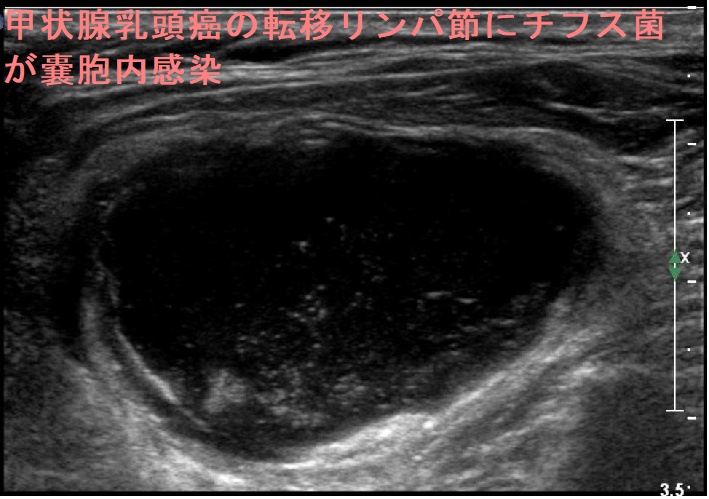

甲状腺乳頭癌の転移リンパ節にチフス菌(Salmonella Typhi)が感染(嚢胞内感染)し、サルモネラ誘発性頸部膿瘍を発生した報告があります。[Case Rep Med. 2017;2017:5670429.]